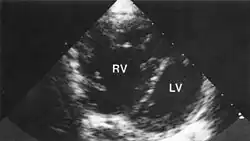

По мере прогрессирования у больных лёгочным сердцем наступают сдвиги кислотно-щелочного состояния, которые первоначально компенсированы, но в дальнейшем может наступить декомпенсация нарушений. Основными признаками лёгочного сердца являются увеличение размеров правого желудочка и изменения в крупных сосудах малого круга в виде переразвития мышечной оболочки, сужения просвета с последующим склерозированием. В мелких сосудах нередко обнаруживаются множественные тромбы. Со временем в увеличенном и изменённом миокарде развиваются дистрофические и некротические изменения.